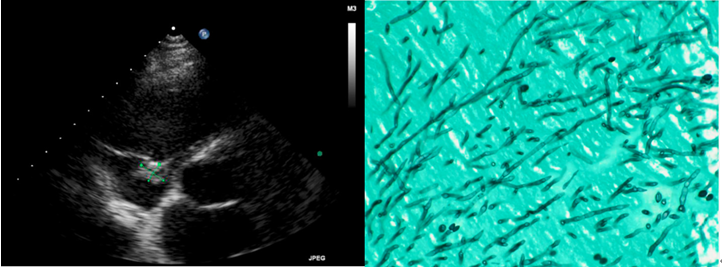

注:尖端赛多孢引起真菌性心内膜炎(心脏移植患者)[9]

患者,男性,38岁,以“食欲下降4月,发现颈部淋巴结肿大1月余”就诊感染科。查体:神清、消瘦,贫血貌。额头可见散在淡红色丘疹,双肺呼吸音粗。右侧颈部前侧触及多个淋巴结肿大,大的可至2 cm×2 cm。口腔上颚可见白斑。余未见异常。WBC 3.84×109/L,Hb 70.0 g/L(↓),NE% 83.1%,PCT 0.338 ng/ml(↑),CRP 13.84 mg/L(↑)。PET提示:①左颈部、左锁骨区、双侧腋窝、肝门区、腹膜后、肠系膜、盆腔、双侧腹股沟多发高代谢淋巴结,结合病史考虑炎性改变(肉芽肿性病变?其他?);②双肺散在微小结节,代谢不高,建议CT复查;③肝脏增大,轻度脂肪肝,肝内未见异常高代谢病灶;④脾脏增大,腹盆腔少量积液;⑤双肾细小结石;⑥右侧锁骨胸骨端、右侧肩胛骨骨质密度欠均匀,代谢增高。淋巴结穿刺可见腊肠样分生孢子(黑色箭头所示),同时还发现了念珠菌(蓝色箭头所示)。提示临床医生查HIV,结果显示HIV阳性,血培养阴性。

图片

荧光染色可见典型的腊肠样分生孢子(下图中红色箭头所示)。早期文献分析报道中国有组织胞浆菌流行,但最后发现其中很多都是将马尔尼菲篮状菌误诊为组织胞浆菌,在骨髓涂片中,如果不是经验非常丰富临床医生,很容易将组织胞浆菌和马尔尼菲篮状菌混淆而导致误判,但如果在荧光染色下发现腊肠样分隔孢子,则可判断是马尔尼菲篮状菌。组织胞浆菌目前在国内非常罕见。